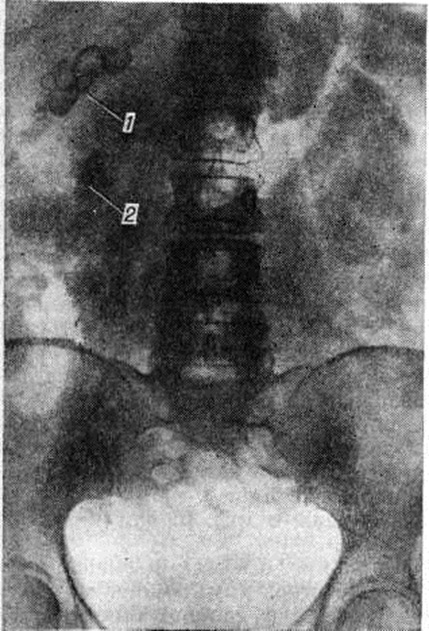

Рис. 5.

Правосторонняя пневмопиелотомограмма: стрелкой указана тень камня в нижней чашечке на фоне газа, заполнившего лоханку и мочеточник.

Рис. 6.

Левосторонняя ретроградная уретерограмма: стрелкой указан дефект наполнения, обусловленный камнем, расположенным в нижней трети мочеточника.

Рентгенологические метод является основным в диагностике Почечнокаменная болезнь Он позволяет выявить не только наличие камней, но и установить их форму, величину, локализацию, структуру, а также получить представление об изменениях в анатомо-функциональном состоянии почек и мочевых путей. Исследование начинают с обзорной рентгенографии брюшной полости, начиная от ThXl до лонного сочленения. Обнаружение на обзорной рентгенограмме тени, подозрительной на конкремент, не требует дифференциальной диагностики только в случае коралловидного камня, являющегося слепком чашечно-лоханочной системы (рисунок 2). Камни почечных чашечек представляют собой их слепки или имеют неправильную, округлую форму; камни почечной лоханки часто округлые или треугольные; камни мочеточника — цилиндрической, веретенообразной или неправильной формы. При аномалиях мочевых путей конкремент может находиться вне обычной локализации почек и других органов мочеполовой системы. Обнаружение камня на снимке зависит от его размеров, химический состава и локализации. Наиболее интенсивное изображение дают оксалаты, затем камни смешанного состава и фосфаты. Оксалаты имеют шиповидные, фестончатые контуры и напоминают тутовую ягоду. Коралловидные камни чаще всего компактны, но могут быть слоистыми, как и остальные конкременты смешанного состава, иногда они достигают гигантских размеров. Слоистое строение камней на рентгенограммах обусловлено различной проницаемостью для рентгеновского излучения составляющих их солей. Около 10% камней с низким атомным весом (ураты, белковые, цистиновые и ксантиновые камни) не видны или дают неотчётливую тень. Особенно трудно выявить камни, проецирующиеся на костный скелет (ребра, поперечные отростки позвонков, крестцово-подвздошные сочленения). Для их обнаружения производят прицельные снимки в косых и атипичных проекциях, томо или зонографию. Томография (смотри полный свод знаний), применяемая самостоятельно или в сочетании с контрастными исследованиями, показана при недостаточной подготовке больного к рентгенологическое исследованиям, почечной колике, сопровождающейся парезом кишечника, или при малых размерах камней. Поскольку при Почечнокаменная болезнь довольно часто конкременты самопроизвольно отходят из чашечно-лоханочной системы, они могут проецироваться по ходу мочеточника паравертебрально, имеют тенденцию задерживаться над одним из его анатомических сужений. Наиболее важные сведения о принадлежности выявленной тени к мочевым путям, о локализации камня, вызванных им нарушениях функции почек, уродинамики, анатомического состояния мочевых путей (гидрокаликоз, пиелэктазия, гидроуретеронефроз — расширение чашечек, лоханки, мочеточника и почки) выявляются при экскреторной урографии (рисунок 3, б) с предварительной обзорной рентгенографией (рисунок 3, а). Она позволяет установить вид лоханки (открытая или закрытая, внутрипочечная или внепочечная), состояние лоханочно-мочеточникового сегмента (смотри полный свод знаний: Пиелография). Обычно рентгенопозитивный конкремент определяется в мочевых путях, но иногда его изображение перекрывается, как бы тонет на фоне контрастированной мочи, особенно при небольшом камне или малой интенсивности его изображения. При рентгенонегативных камнях виден дефект наполнения мочевых путей (в том числе и лоханки) с чёткими контурами (рисунок 4). В отличие от опухоли лоханки в косых проекциях вокруг камня сохраняется ободок контрастного вещества. Обычно при камнях лоханки, достигающих в диаметре 3 сантиметров и более, наблюдаются пиелэктазия и гидрокаликоз. Произведённые в процессе экскреторной урографии телевизионная пиелоуретероскопия в сочетании с кинематографией или видеомагнитофонной записью изображения позволяют оценить нарушения тонуса и моторной функции верхних мочевых путей при камнях, отличить спастические, функциональный процессы от органических. Если спустившийся в мочеточник камень частично закрывает его, то отмечаются расширение мочеточника и лоханки (пиелоуретерэктазия) выше уровня расположения конкремента. На экскреторных урограммах, произведённых во время почечной колики, выявляется увеличенная почка с усиленным нефрографическим эффектом без контрастирования чашечно-лоханочной системы и мочеточника — так называемый большая белая почка. Такая рентгенологическое картина указывает, что функция почки сохранена. При длительной полной блокаде камнем (более 3—4 недель) функция почки из-за атрофии снижается и может полностью утрачиваться. На экскреторных урограммах, произведённых после почечной колики, иногда наблюдается проникновение контрастированной мочи за пределы мочевых путей, а также лоханочно-почечный рефлюкс. Ретроградную пиелоуретерографию с жидким контрастным веществом или кислородом производят только при значительном снижении функции почек, при сомнении в диагнозе, особенно в тех случаях, когда при экскреторной урографии не выявляется рентгенонегативный камень. Рентгенографию мочеточника после введения в него катетера производят в прямой и косой проекциях. Если при этом тень, подозрительная на камень, на обоих снимках находится рядом с катетером или сливается с его тенью, то диагноз Почечнокаменная болезнь не вызывает сомнений. Тень, не относящаяся к мочеточнику, определяется на некотором расстоянии от катетера. На ретроградных пиелограммах с жидким контрастным веществом небольшой концентрации рентгенонегативные камни выявляются в виде дефекта наполнения. Особенно демонстративными такие камни становятся при пневмопиелорентгенографии или пневмопиелотомографии (рисунок 5). С помощью ретроградной уретерографии удаётся выявить рентгенонегативный камень в мочеточнике, верхние границы дефекта при этом имеют вогнутую форму (рисунок 6).